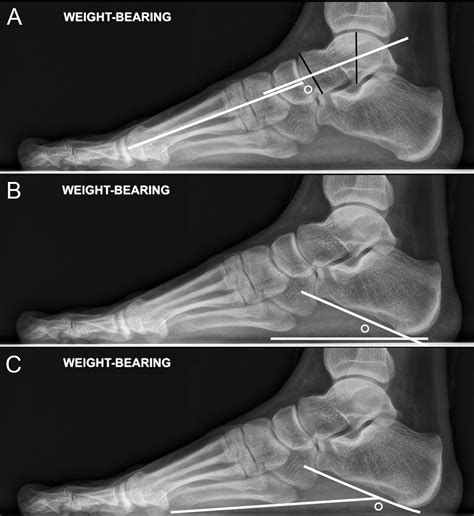

Diagnosing flat feet typically involves a physical examination and possibly imaging tests. A healthcare provider will assess the foot's structure, flexibility, and range of motion. Imaging tests such as X-rays, CT scans, or MRIs may be used to evaluate the bones and soft tissues of the foot.

During the examination, the healthcare provider may ask the patient to stand on their toes or walk to observe the foot's arch and movement. They may also check for signs of inflammation, swelling, or tenderness.